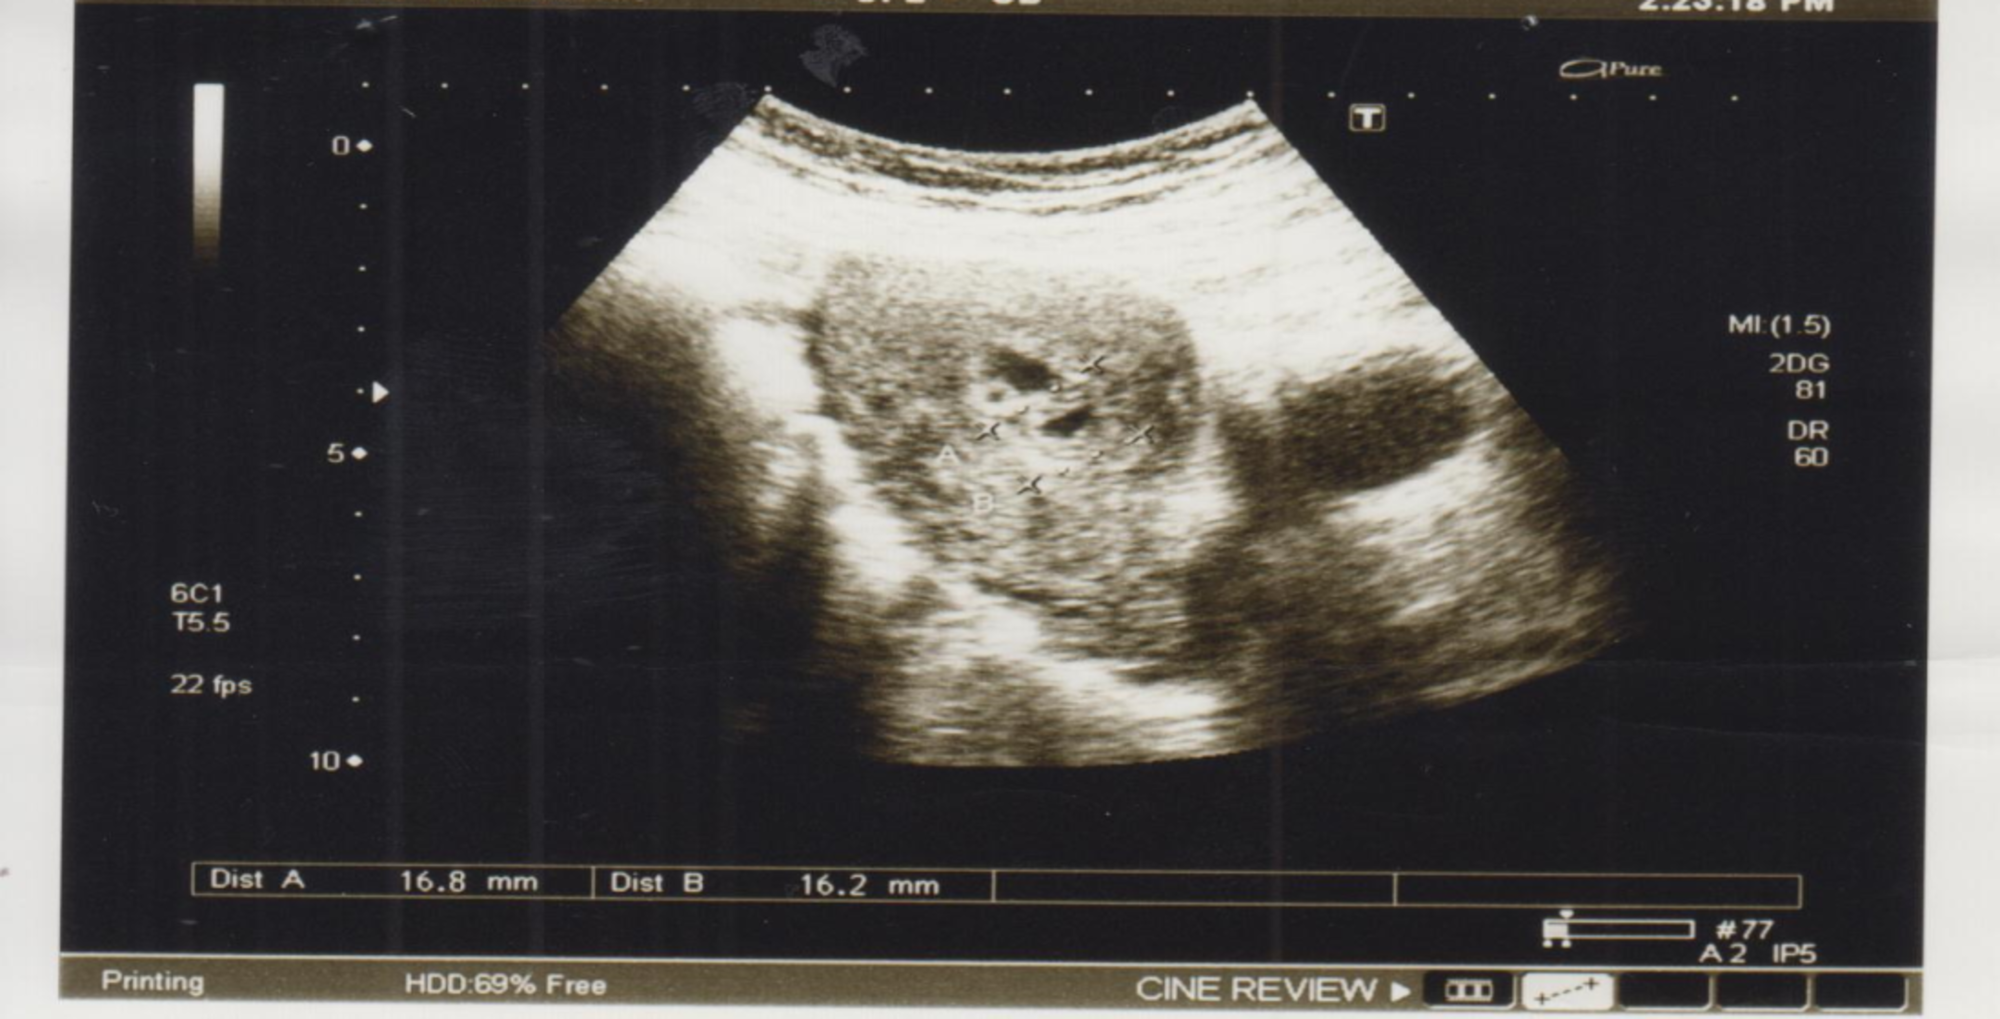

Ultrasound images of a female patient, aged 55years with thickened... Download Scientific Diagram Thickened Endometrium With Increased Vascularity When the endometrium shows up on an mri or ultrasound, it looks like a dark stripe, sometimes called the endometrial stripe. Endometrial hyperplasia refers to the thickening of the endometrium. To investigate the correlation between sonographic, hysteroscopic, and pathological findings in postmenopausal asymptomatic patients with. Having an abnormally thick endometrium could be an early sign of cancer. This is the. Thickened Endometrium With Increased Vascularity.

Ultrasound showing thickened endometrium Download Scientific Diagram Thickened Endometrium With Increased Vascularity This is the layer of cells that. Having an abnormally thick endometrium could be an early sign of cancer. To investigate the correlation between sonographic, hysteroscopic, and pathological findings in postmenopausal asymptomatic patients with. Other symptoms include heavy, frequent, or otherwise irregular bleeding, irregular discharge. In some women, this can. When the endometrium shows up on an mri or ultrasound,. Thickened Endometrium With Increased Vascularity.

] Ultrasound image showing thickened endometrium Download Scientific Diagram Thickened Endometrium With Increased Vascularity When the endometrium shows up on an mri or ultrasound, it looks like a dark stripe, sometimes called the endometrial stripe. Other symptoms include heavy, frequent, or otherwise irregular bleeding, irregular discharge. This is the layer of cells that. To investigate the correlation between sonographic, hysteroscopic, and pathological findings in postmenopausal asymptomatic patients with. Endometrial hyperplasia is a condition in. Thickened Endometrium With Increased Vascularity.